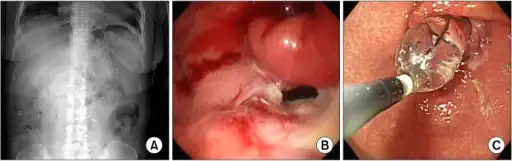

-

a-c)Radiologic and endoscopic finding of delayed gastric emptying -

GI monitoring capsule